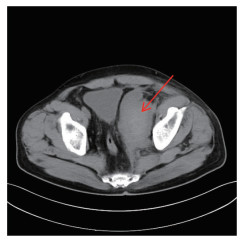

全腹增强CT检查结果显示,左侧盆壁可见约11.3 cm×5.5 cm团片状血性密度影,CT值32~63 Hu,增强扫描未见确切强化。影像学诊断为左侧盆壁血肿可能性大(图 1)。

| 图 1 病例1增强CT图像 |